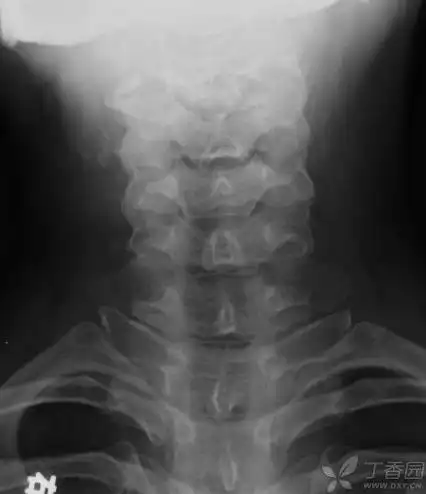

今天的一个病例肋骨分叉

颈肋畸形

双侧颈肋并肋骨间骨性联合

70岁.很典型的颈肋.

多出一对肋骨的情况多见于女性,又称为颈肋,可以是一小段,也可能是整